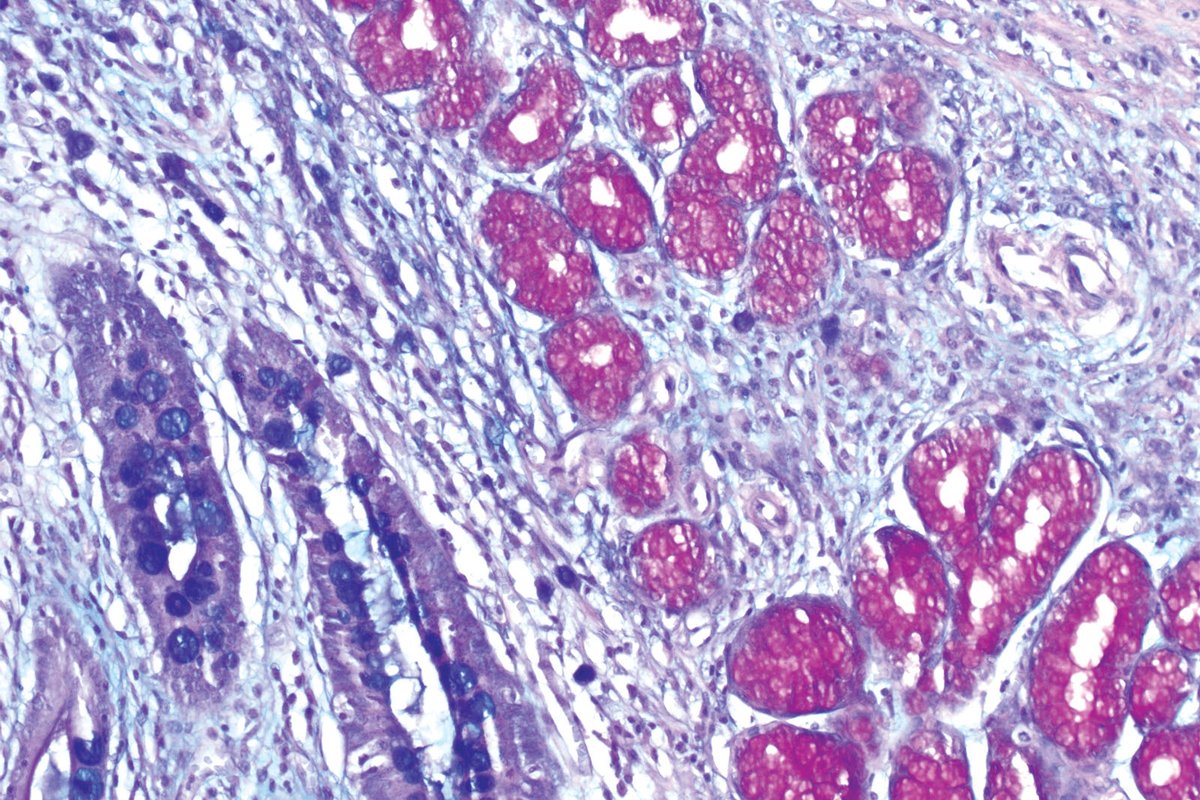

📌 Masson Trichrome

يستهدف الانسجة الضامة

Collagen ويظهر بالازرق\الاخضر

Muscle يظهر بالاحمر

Reticulin اخضر مزورق

Fibrin احمر